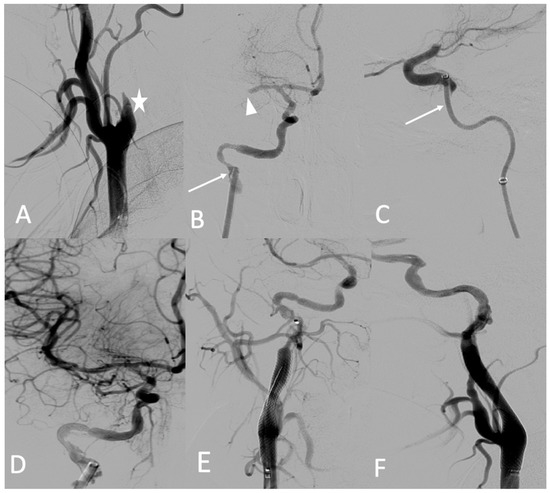

A 25-year-old female patient with pre-symptomatic vEDS was referred to our hospital for acute left-sided hemiplegia and transient right arm hemiparesis. Magnetic resonance imaging (MRI) cerebral and CT angiography of the supra-aortic trunk demonstrated a sub-occlusion of the right middle cerebral artery, along with a severe hypoperfusion of the right internal carotid artery related to dissection and an intramural hematoma of the left internal carotid artery. Her medical status was a contraindication to thrombolysis, and the stroke team decided to refer her to the interventional neuroradiologist. Under general anesthesia, an 8 F introducer was inserted via the right femoral artery. Right common carotid artery access was obtained using a 7 F NEURON MAX catheter (Penumbra-Alameda, CA, USA) and a TERUMO 0.035 guidewire. DSA revealed an occlusion of the dissected right internal carotid artery and an occlusion of the proximal portion of the middle cerebral artery (M1) (Figure 6A). Aspiration through a dedicated catheter (Sofia 6 F TERUMO) of the M1 thrombus was unsuccessful (Figure 6B,C). The thrombus was then successfully removed using a Headway microcatheter (0.027), Terumo microwire (0.016), and stent retriever (Solitaire 4 × 20), with good outcome (Figure 6D). The right internal carotid artery dissection was treated through the deployment of a 7 × 50 mm carotid wall stent in the extracranial portion of the right internal carotid artery (Figure 6E,F).

Figure 6.

(A) Digitally subtracted image from the right common carotid angiogram showing occlusion over the dissection of the right internal carotid artery (star); (B,C) crossing the dissection by a Sofia 6 F aspiration catheter (arrows) and the occlusion of the proximal portion (M1) (arrowhead); (D) anterior view after mechanical thrombectomy; (E,F) anterior and lateral views after the deployment of the carotid wall stent.

No complications occurred during the procedure or during the postprocedural hospital stay. A few months later, she developed a dissecting aneurysm in the right internal carotid artery after the stent, which was monitored by Doppler ultrasound. After 3 years of follow-up, she did not have any other arterial event under celiprolol therapy and presented with persistent left hemiparesis.